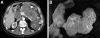

Summary background data: Serous cystadenoma of the pancreas is the most common benign pancreatic neoplasm. Diagnostic criteria, potential for growth or malignancy, and outcomes are not well defined. As a result, management for patients with serous cystadenomas varies widely in current practice.

Methods: A total of 106 patients presenting with serous cystadenoma of the pancreas from 1976-2004 were identified. Hospital records were evaluated for patient and tumor characteristics, diagnostic workup, treatment, and outcome. Twenty-four patients with serial radiographic imaging were identified, and tumor growth curves calculated.

Results: Mean age at presentation was 61.5 years and 75% of patients were female. The most common symptoms were abdominal pain (25%), fullness/mass (10%), and jaundice (7%); 47% were asymptomatic. Mean tumor diameter was 4.9 +/- 3.1 cm, which did not vary by location. Tumors <4 cm were less likely to be symptomatic than were tumors > or =4 cm (22% vs. 72%, P < 0.001). The median growth rate in the patients who had serial radiography was 0.60 cm/y. For tumors <4 cm at presentation (n = 15), the rate was 0.12 cm/y, whereas for tumors > or =4 cm (n = 9), the rate was 1.98 cm/y (P = 0.0002). Overall, 86 patients underwent surgery, with one perioperative death.